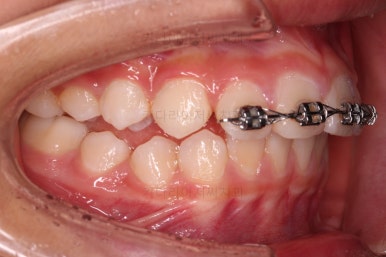

부산소아교정 초진 시 입안의 모습입니다.

윗니가 아랫니보다 많이 앞에 나와있고요.

심지어는 틈새가 벌어지기까지 했습니다.

윗니가 배열 되어있는 U자 형태(그릇 형태)가 아랫니보다 좁은 양상이고요.

이런 앵글씨 2급 부정교합에서는 아랫니가 윗니와 만나기 위해 솟구쳐서 과개교합(아래 앞니가 윗니 뒤쪽으로 깊숙히 올라가 있는 상태)이 나타나기까지 합니다.